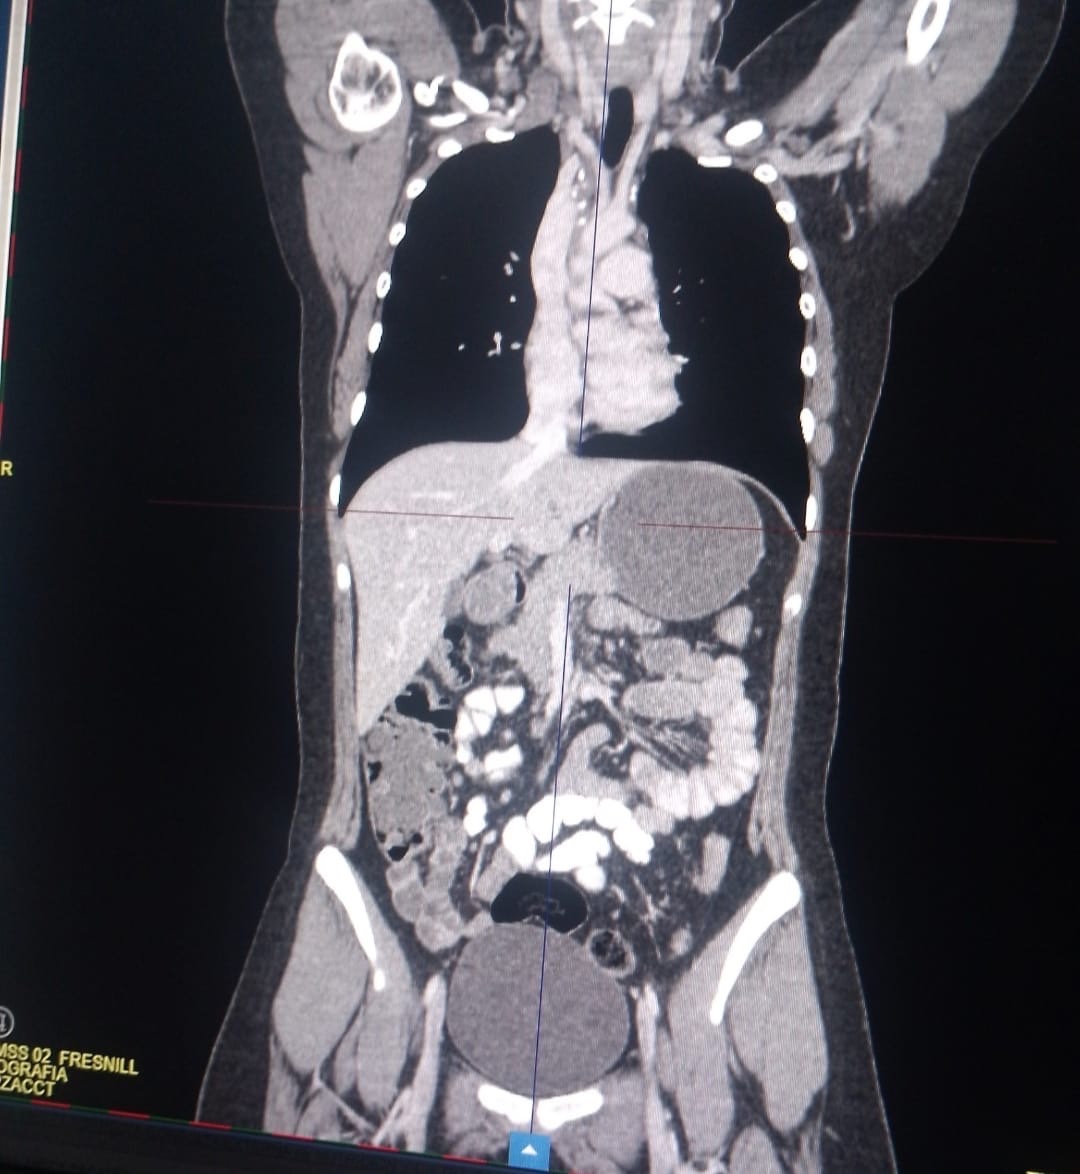

• añadí unas tomografías y ahí se ve como empecé y como salió una de mis últimas tomografías